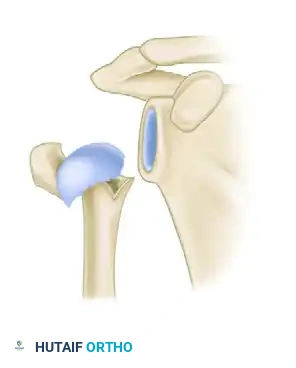

| كسر الجزأين | جزء واحد فقط من العظمة انفصل وتحرك من مكانه، مثل كسر عنق العظمة أو كسر الحدبة الكبرى. |

إليك بعض الصور الإشعاعية والرسوم التوضيحية الإضافية التي توضح أشكال التثبيت الجراحي المختلفة لكسور أعلى عظمة العضد